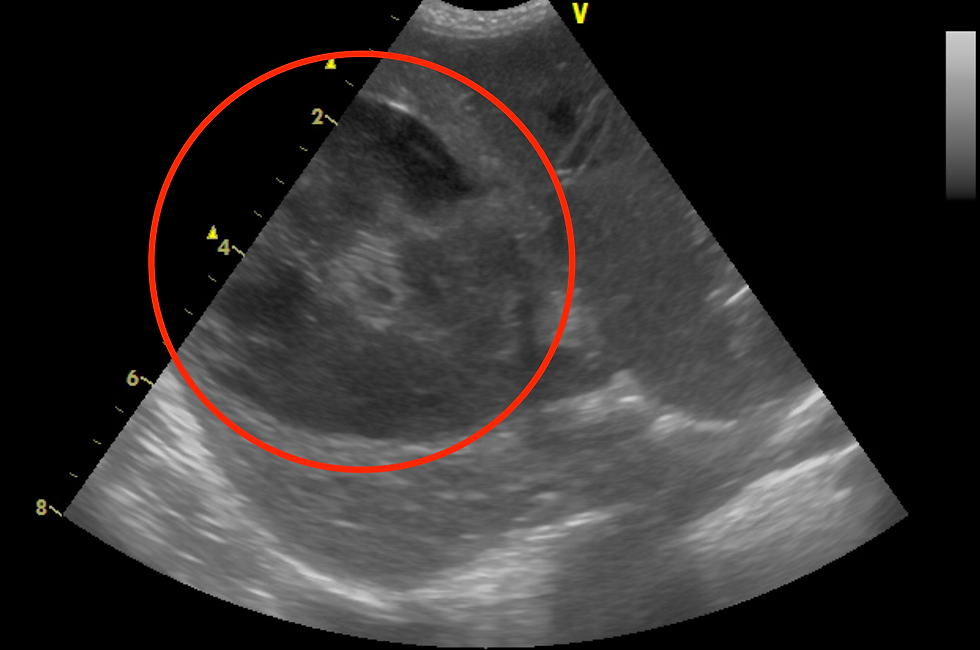

超音波検査で見つかった胆嚢粘液嚢腫

(赤丸印)

後に手術で胆嚢を摘出しました。